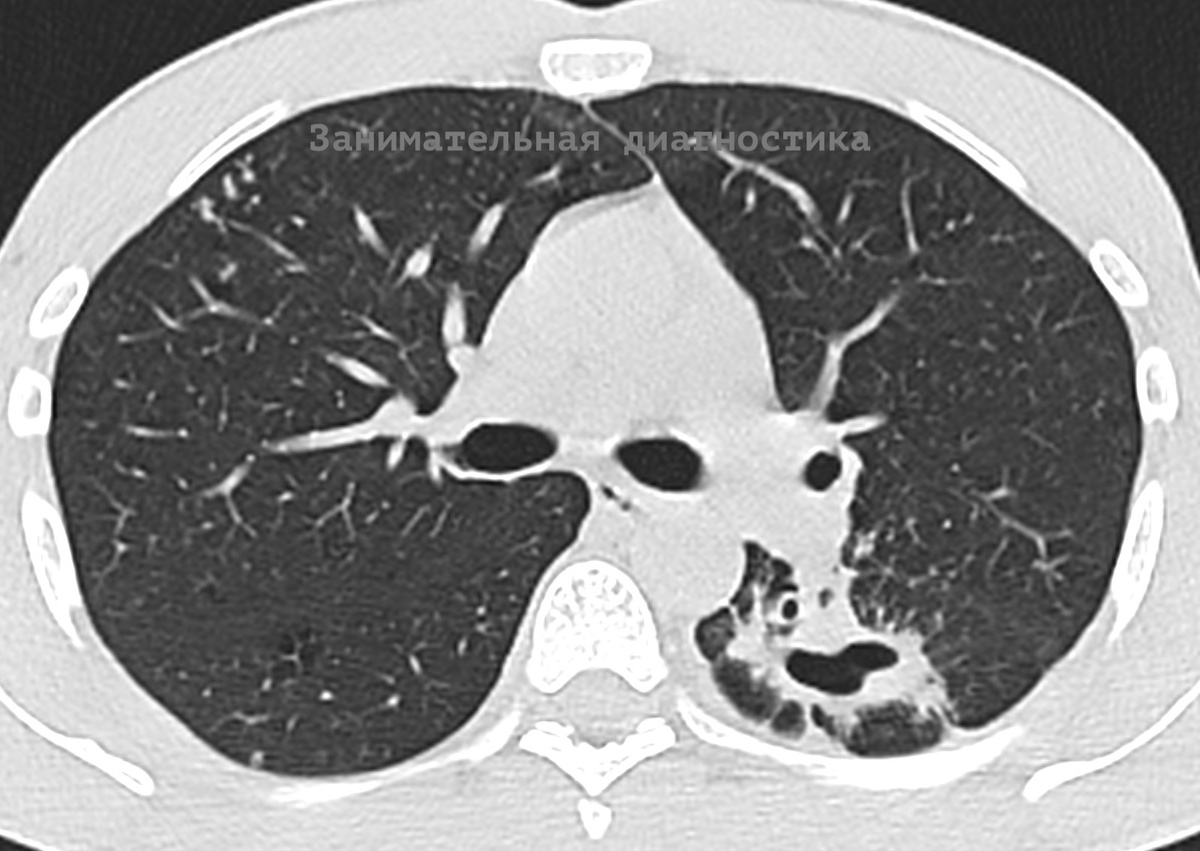

Молодой мужчина 32 лет обратился с жалобами на слабость, длительный кашель и невысокую температуру.

На КТ выявлен двухсторонний воспалительный процесс в лёгких, преимущественно в верхних долях, полость распада в нижней доле левого лёгкого.

Налицо типичная картина запущенного туберкулёза.